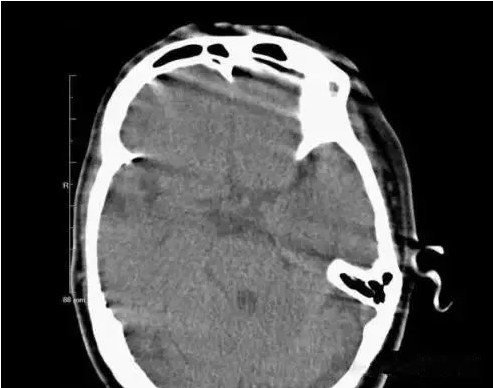

(運動偽影)

在掃描過程中,如果病人體位發(fā)生變化,可造成圖像數(shù)據(jù)排列紊亂。重建圖像結(jié)構(gòu)模糊,無法分辨。運動偽影又分為自主運動偽影和生理性運動偽影。